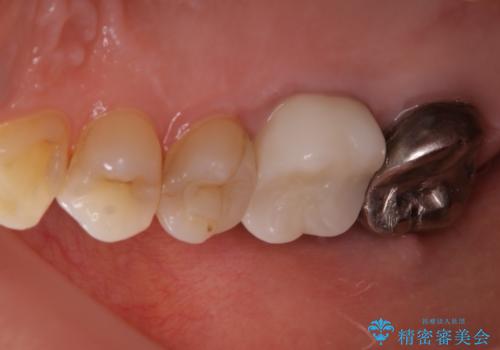

根管治療を再度行うことでフィステル(ニキビのようなできもの)は消失しました。最終的にセラミッククラウンによる補綴治療を行いました。

被せ物について

適合不良の補綴物は二次的な虫歯発生のリスクが高まります。

自費診療で用いられる材料は保険適応の材料に比べて、より精密で適合の良い被せ物作ることができるため、長期的な虫歯のリスクを大幅に減らすことが可能です。

セラミック治療の注意事項(リスク・副作用など)

- 天然歯を削ります

- 硬い素材は天然歯を傷つけてしまう場合があります

- かみ合わせや歯ぎしりが強すぎる方はセラミックが割れてしまう可能性があります

- 自費診療(保険適用外治療)となります